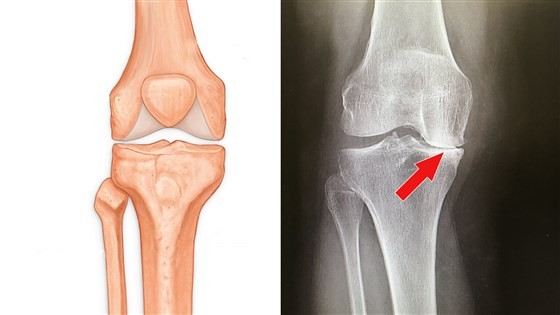

من علامات خشونة الركبة عندما يتقابل عظم الظنبوب مع عظم الفخذ والدرع الواقي للرضفة ، ويأتي ذلك لتحميل الجسم على منطقة الركبة ، مما قد يؤدي إلى حدوث بعض التآكل للركبة أو قطع في الأوتار في بعض الحالات الأخرى[2].إلا أنه قد يوجد في تلك المنطقة  قطعتان من الغضاريف تمتص للصدمات ، وتعمل وكأنه وساده بين عظام الساق والفخذ ، وتتعبر تلك القطعتين الغضروف المفصلي ، وتلك المنطقة تحتوي على عضلات الفخذ والغضروف المفصلي وأوتار الرضفة .وقد تضغط على ركبتك دون الشعور بأي ألم ويكون ذلك نتيجة لفقاعات الغاز ، وكذلك بسبب تغير الضغط الذي يحدث في منطقة مفصل الركبة ، التي تتراكم فيها فقاعات الغاز الصغيرة التي تتواجد في تلك المنطقة .ويحدث انفجار لتلك الفقاعات ، مع التحرك بصورة صغيرة وينتج عن ذلك صوت الفرقعة ، كما يمكن حدوث ذلك من الركبتان الصاخبة عن تمدد الرباط أو الوتر فوق كتلة عظمي .ويتم سماع عدد من الضوضاء وخاصة في حالة ما إذا أستمر النسيج في مكانه ، وقد يكون التحرك الذي يحدث في النسيج الندبي، من أعلى العظام ، ينتج عنه سبب أخر لحدوث طقطقه دون ألم .

ويحدث ذلك عند وجود طقطقه في الركبه ، ويصطحب ذلك حدوث ألم وتورم أو الاحساس بالخرج في الركبة أو القبض في منطقة المفصل ، ويكون ذلك مسببا لعدد من الأمور .والتي يكون منها بعض الاصابات الخطيرة حول الركبة وتزداد الخطورة حال عدم العلاج للألم بالشكل الصحيح ، مما قد يطور عدد من الأنسجة غير الهامة حول الركبة ، وقد تتشابك الأنسجة مع أجزاء المفصل ويسبب عدد من الازعاج عند المفصل .وفي حال ركبة العداء رغم أن الجري قد يكون مفيد ، ولكن عندما تضغط بشكل دائم ، على قصبة الساق فقد يؤذي ذلك ركبة العداء وتكون الرضفة خارج الخط وتكون في شكل غير صحيح له .ورغم أن العظام السفلية وعظام الساق تعمل على حماية الرضفة ، ولكن قد يتم محاذاة تلك العظام بالشكل الصحيح له فالركبة قد تنقر عند ثنيها ، ويعرف هذا بمسمى تلين الغضروف .والتفاوت في منطقة الرضفة يعرف في وقتنا الحالي باسم متلازمة ألم الفخذ الرضفي ، ويتم الشعور بذلك النقر خاصة عند وضعية الجلوس في القرفصاء .الضرر البالغ الذي قد يحدث بالغضروف المفصلي والامتصاص للصدمات ، ومن المعروف أن الغضروف المفصلي عبارة عن وسادة بين العظام الموجودة في الركبة ، وقد يتسبب ذلك في دوران الركبة عند الضغط عليها .ويحدث ذلك صوت الطقطقه في الركبه، ويحدث مجموعة من الألم ، خاصة عندما تقوم بتحريك الركبة من الأمام للخلف وهكذا ، وتشعر بذلك أثناء صعود السلالم ونزولها ويأتي الألم لك ويذهب ، فقد يشير ذلك لحدوث الغضروف المفصلي .الكيسات بالغضروف المفصلي ويحدث ذلك عند تمزق الغضروف الهلالي ، ويتم تشكيل تلك الأكياس بصورة رئيسية عند تسرب السائل الزليلي ، من المفصل ويتسرب بجوار الغضروف المفصلي أو بداخله .وقد تم العثور في تلك الحالة على واحد في المئة ل أربعة من المئة ، وذلك عند عمل فحوصات بواسطة الغضروف المغناطيسي على منطقة الركبة .من اسباب طقطقة الركب الهشاشة في العظام فقد يتم إنتشار عدد من الالتهابات للمفاصل ، في الساقين لمنطقة الركبتين ، مما يؤثر على الركبتين وقد يجعلهم منحرفتين وملتهبتين مما قد يحدث مجموعة من الفرقعة والقطقه مع الآلم الدائم .